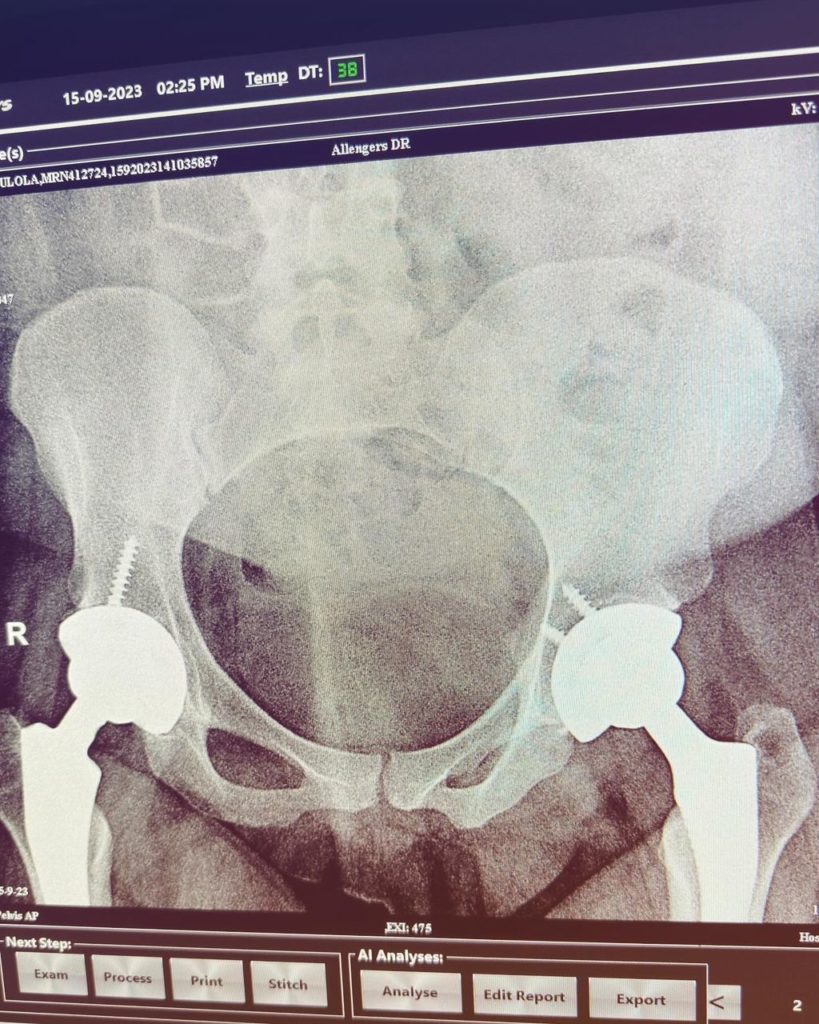

- Avascular necrosis in both hips

Eventually, I got gluteal abscesses from the injections and couldn’t walk. Another surgery revealed I had AVN — Avascular Necrosis. I needed a double hip replacement and couldn’t afford it, so I turned to crowdfunding.

But I’ve also had good doctors. Dr. Laketu diagnosed my AVN at a general hospital. He took his time. He listened. Then there’s Dr. Osawe, who handled my hip surgeries and referred me to every specialist I needed: an endocrinologist, neurologist, psychiatrist, and physiotherapist. He’s made me feel human again. I’ve also met incredible nurses who helped me hold on.